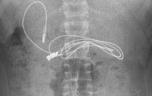

L’endoscopie est une méthode d’exploration qui permet de visualiser et d’extraire un objet dans le tube digestif en introduisant un instrument par les voies naturelles.

80 à 90 % des objets ingérés passent spontanément dans le tube digestif sans nécessiter de manœuvres médicales pour les retirer ; la chirurgie n’est requise que dans moins de 1 % des cas.

QUE FAIRE ? >>